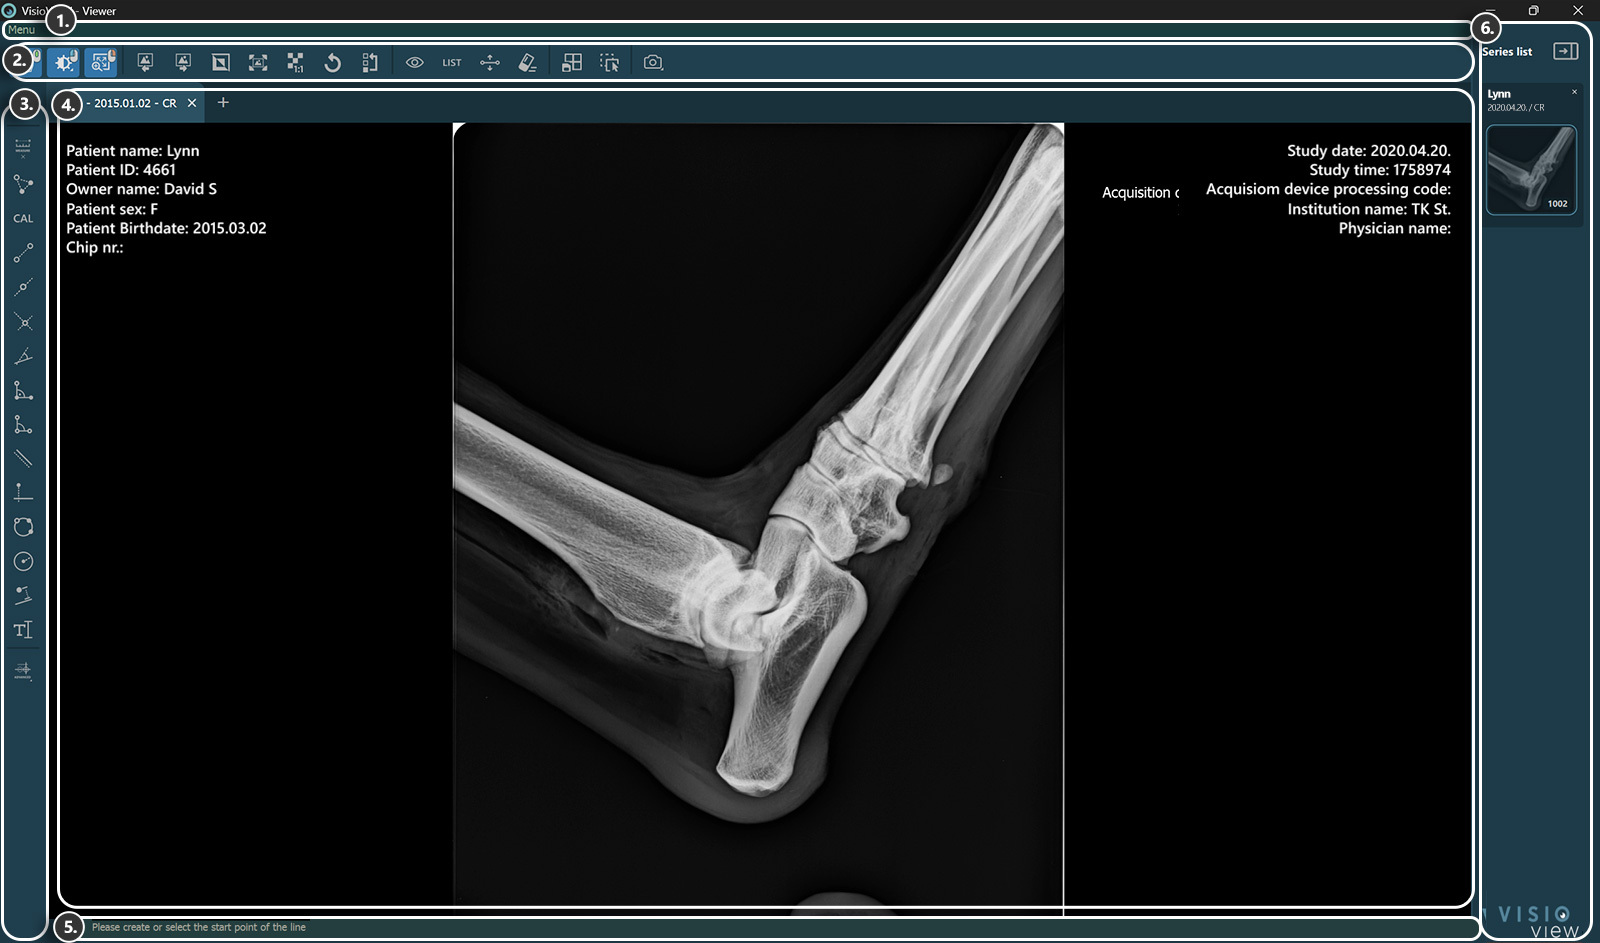

VisioVIEW - Viewer¶

Sections of the VisioVIEW Viewer¶

The VisioVIEW Viewer consists of several sections, each tailored to a specific purpose. Below is a detailed description of each section.

Top Toolbar¶

Left Toolbar - Measurements¶

Simple Measurements¶

Advanced Measurements¶

Viewer Area¶

Information Bar¶